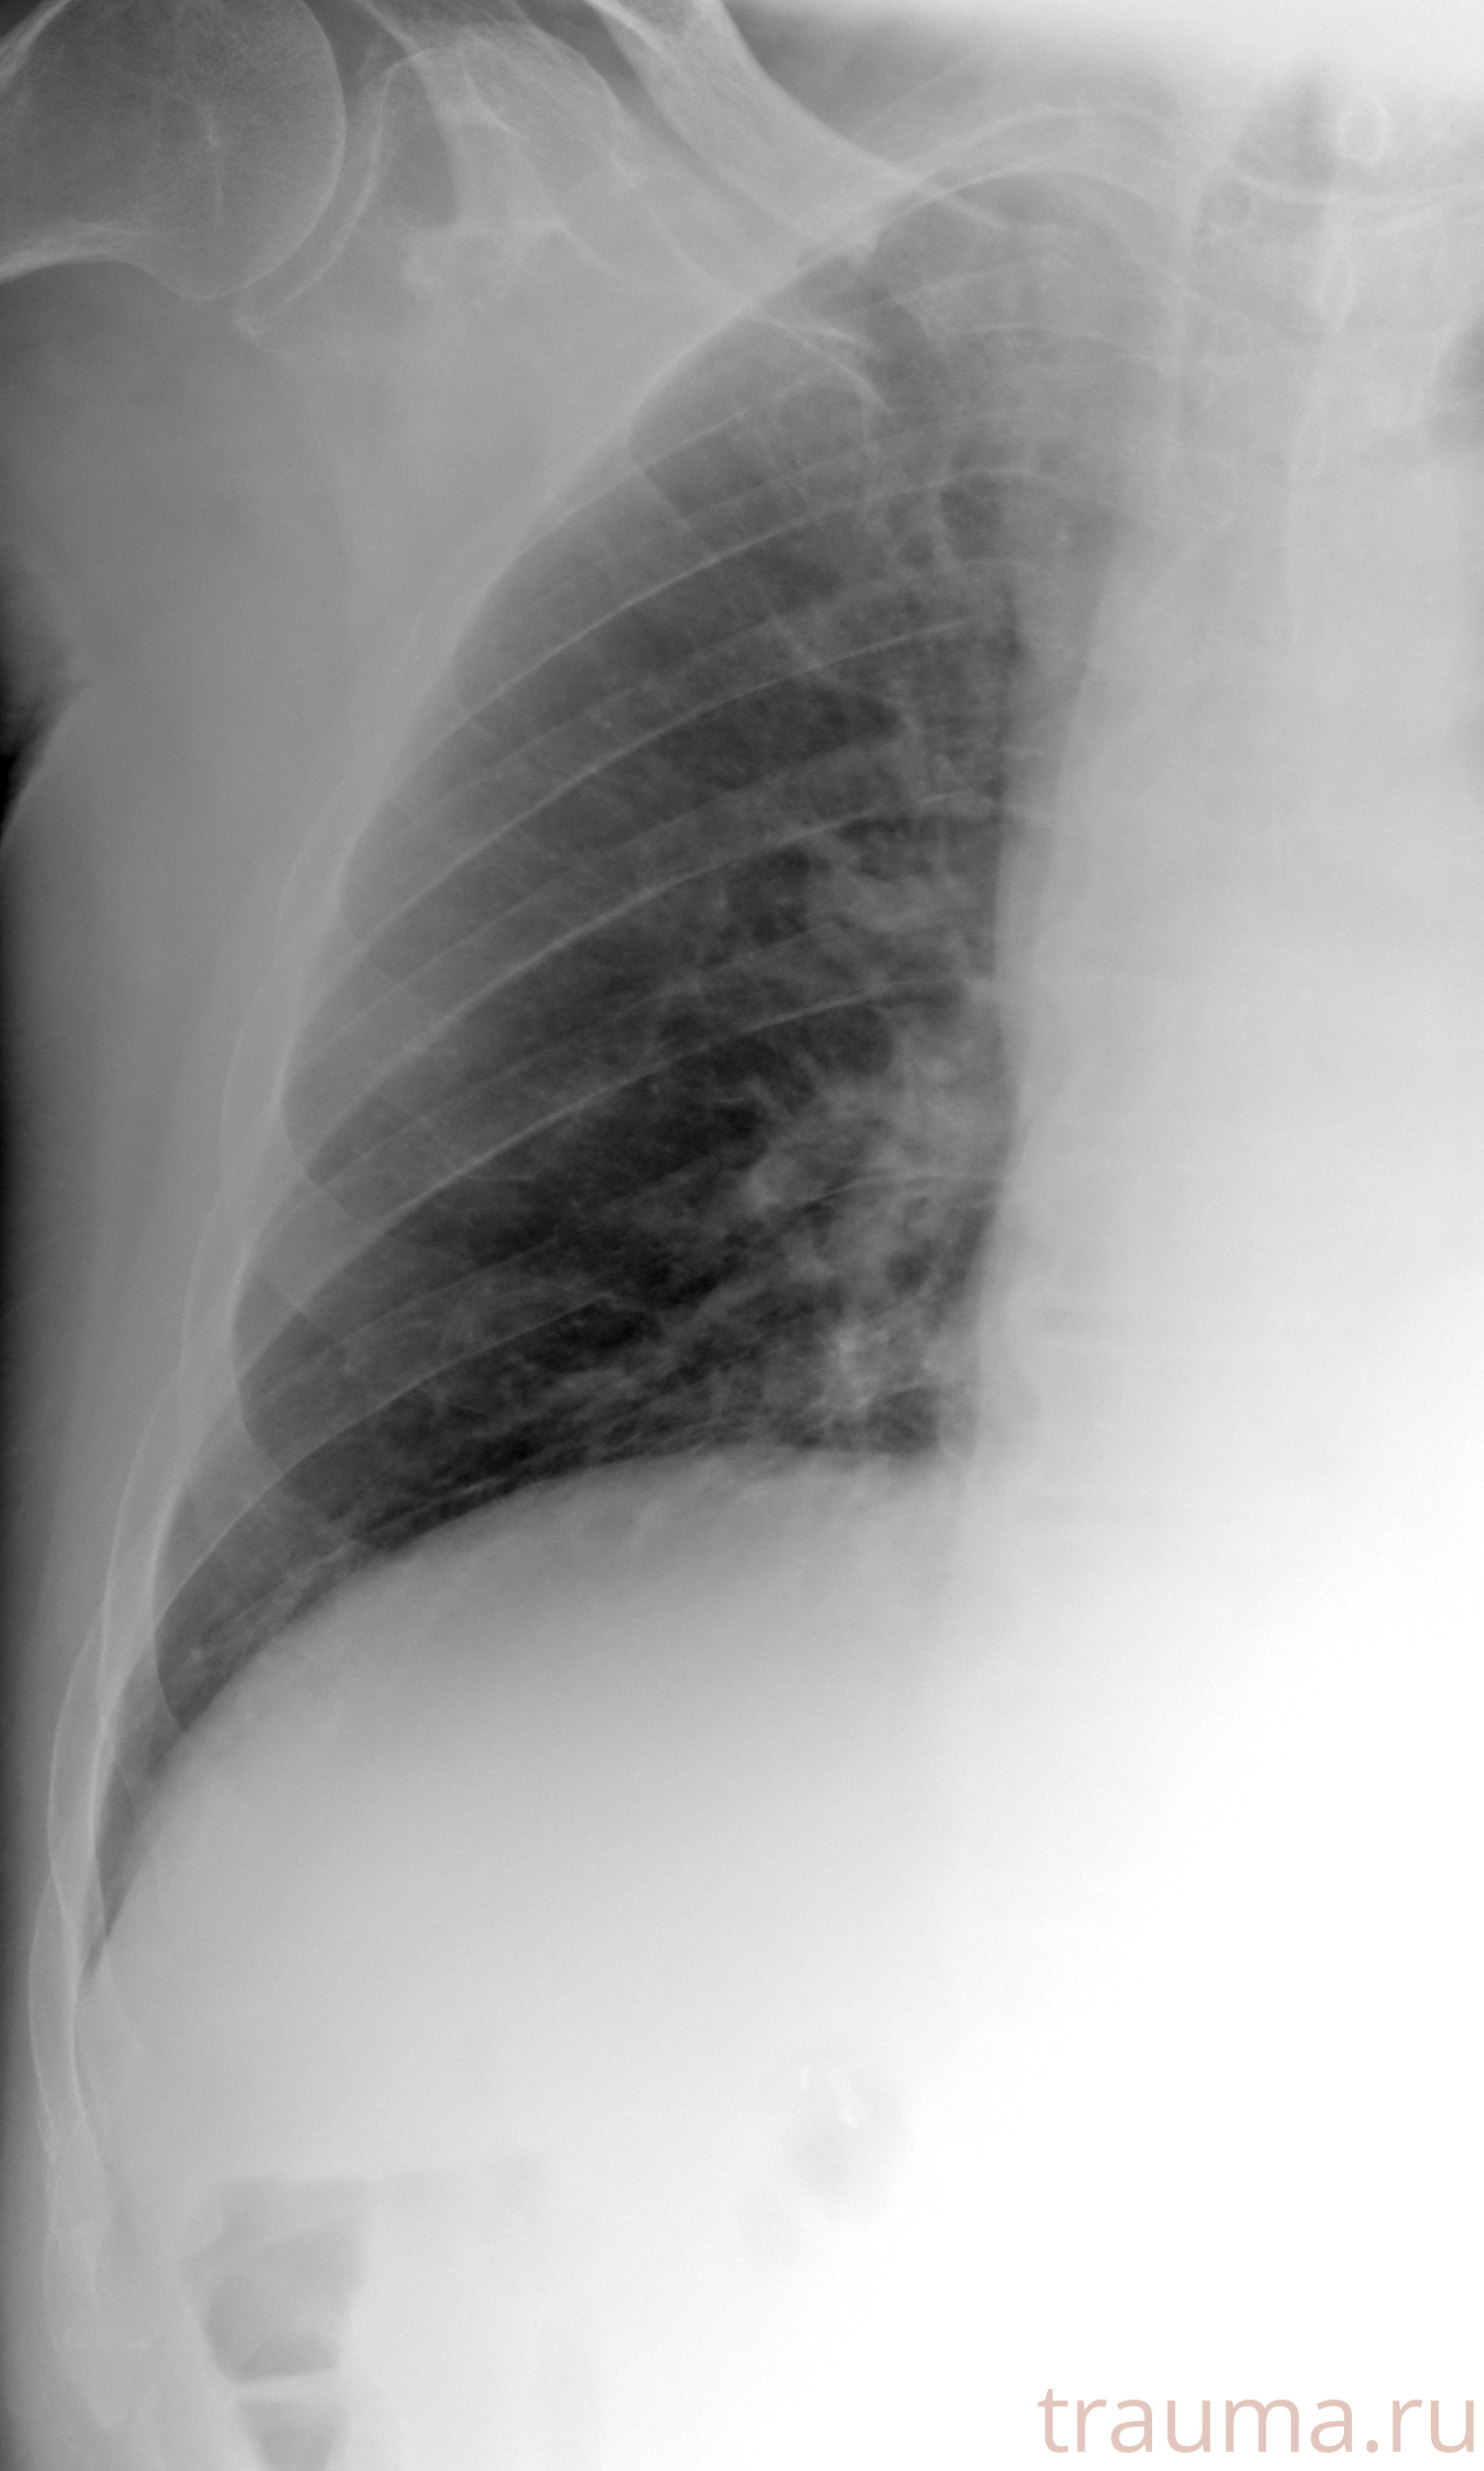

Рентгенограммы

Рентген на дому: по вашему адресу приезжает врач-рентгенолог, травматолог-ортопед с мобильным рентгеновским аппаратом, проводит диагностику травмы или заболевания, делает необходимые рентгенограммы, дает рекомендации по дальнейшему лечению. Получить качественные снимки в домашних условиях возможно благодаря уникальной методике, разработанной МосРентген Центром для института  Склифосовского

при переломе шейки бедра и пневмонии от компании МосРентген Центр - партнера Института имени Склифосовского